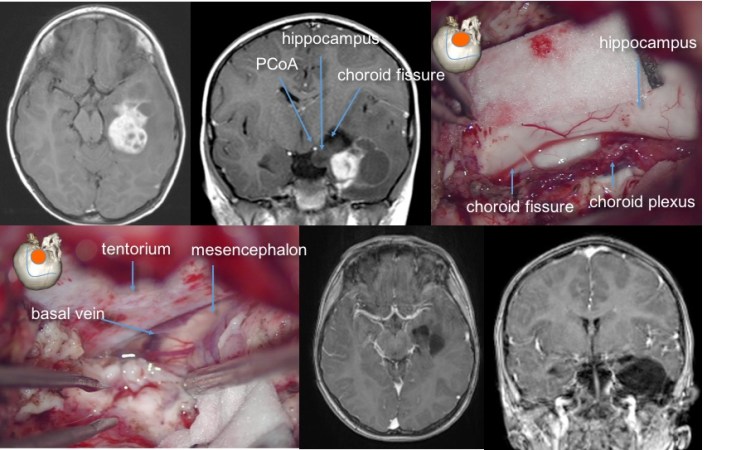

les tumeurs temporales

lorsqu’elles sont situées à la face interne, elle adhérent volontiers au plan vasculo-nerveux interne, englobant parfois le nerf oculo-moteur et pouvant adhérer intimement à la carotide, l’artère communiante postérieure, l’artère cérébrale postérieure. l’imagerie pré-opératoire permet difficilement de prévoir cette difficulté, qui peut interdire une exérèse complète.

la résection anatomique temporo-pôlaire peut être le premier temps d’une résection temporale interne (hippocampectomie) dont l’étendue est dictée par l’extension tumorale, et peut être aidée par l’IRM per-opératoire

les tumeurs localisées à la face interne du lobe temporal plus haut situées, au contact de la bandelette optique, peuvent être abordées en conservant le pôle temporal par un abord trans-ventriculaire trans-T2 (ci-dessous)